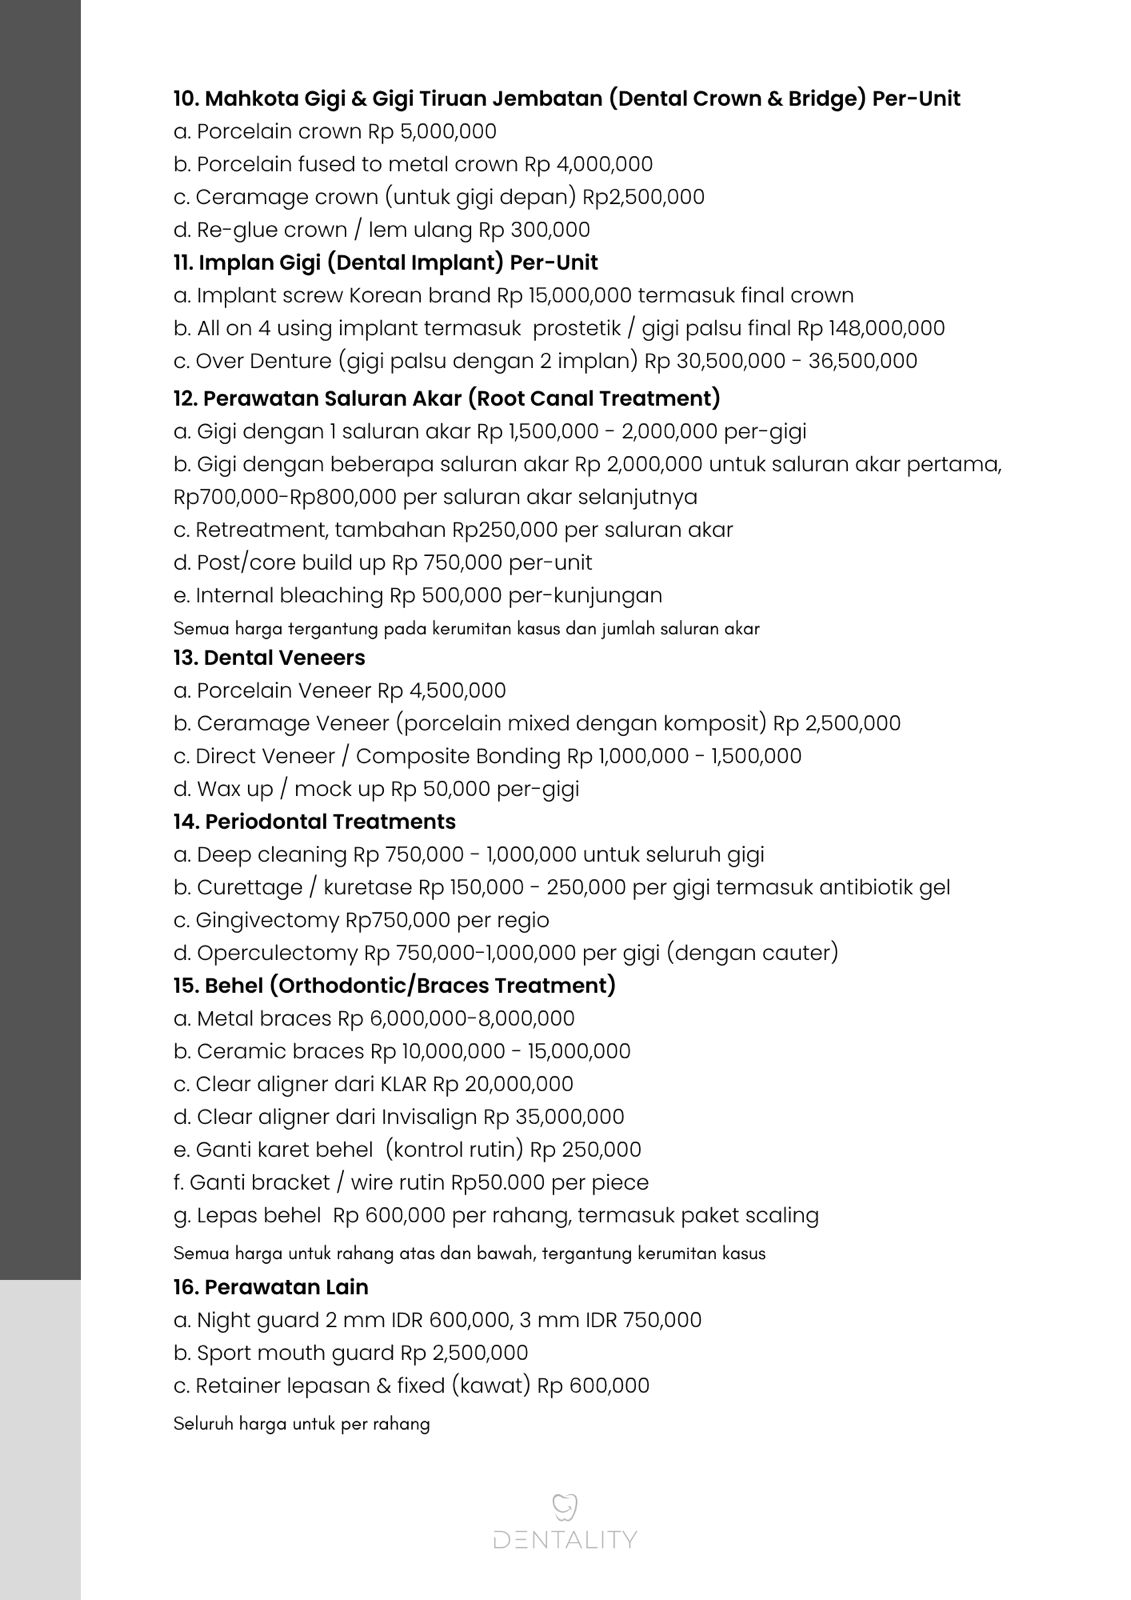

Semuanya, dari scaling, whitening, tambal gigi, hingga implant dan crown gigi.